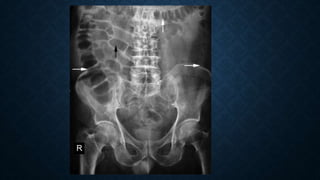

This document provides an overview of x-rays for medical students, covering topics such as ensuring x-rays are well-aligned, exposure levels, common artifacts and anatomical features, abdominal x-ray positions and views, and specialized x-rays including barium swallows, enemas, and tests to examine the esophagus, small bowel, biliary tree, and kidneys.